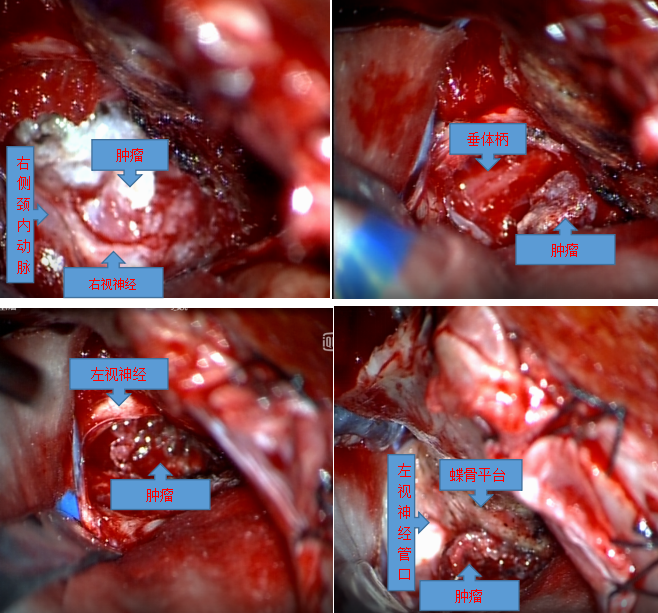

手术过程:麻醉医生贺林春精心细致地为患者实施气管插管全麻,BIS和鼻温监测,以及中心静脉置管,为手术提供安全保障;在贾群英护士长,手术护士乌日罕、樊荣的默契配合下,手术顺利进行,术中见肿瘤基地位于鞍结节,前方向蝶骨平台区生长,两侧包绕颈内动脉及双侧视神经,并向视神经管内生长,后方压迫垂体及垂体柄,向上向后推挤视交叉及三脑室底部,肿瘤色粉红,质地软韧,血供丰富,与视神经粘连严重,显微镜下分块切除肿瘤。术后病理回报砂粒体型脑膜瘤(WHO I)。术后患者视力、视野明显好转,复查头颅核磁肿瘤切除干净。